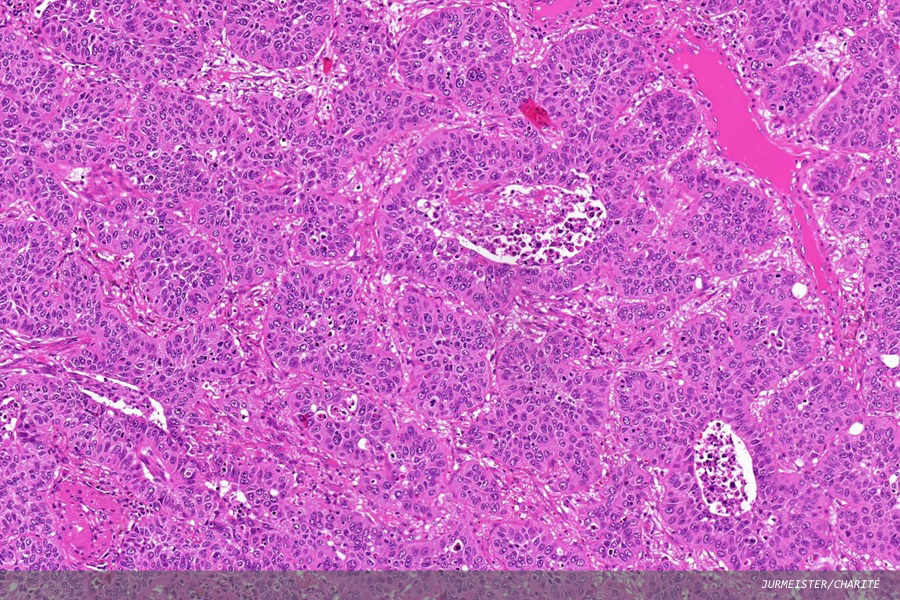

Invasive lung squamous cell carcinoma (LUSC; pictured above) accounts for approximately one-quarter of all lung cancers, but therapeutic options for LUSC remain limited, primarily due to the absence of well-defined, targetable molecular alterations. Therefore, histopathologic features are increasingly being explored as tools to enhance prognostic accuracy and guide treatment decisions.